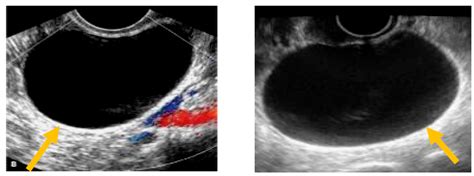

To confirm the presence of an endo cyst ovary, medical professionals typically employ a combination of diagnostic techniques. Because these cysts have a unique appearance on imaging, they are often easier to identify than other types of pelvic growths.

Transvaginal Ultrasound The primary tool used to visualize the cyst's size, shape, and internal fluid characteristics.